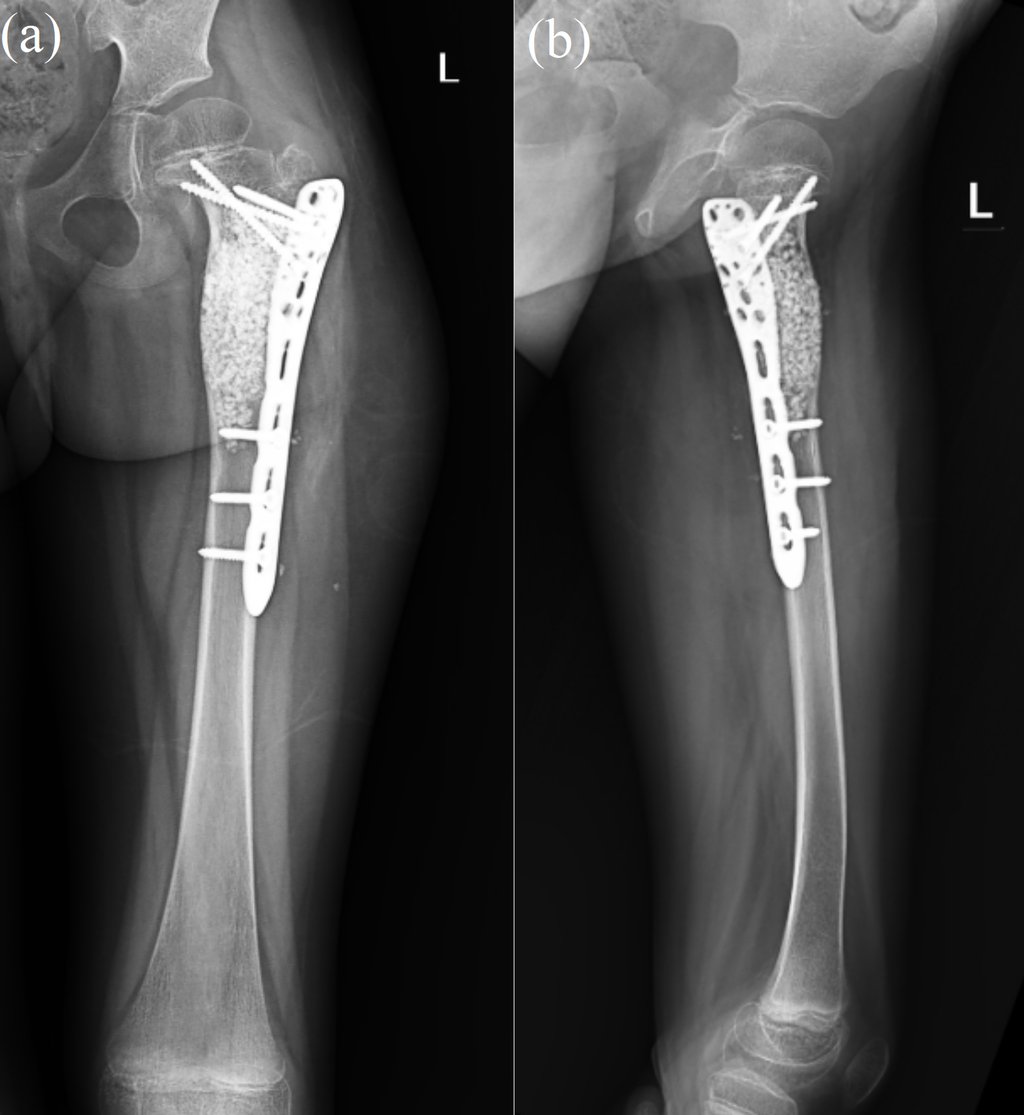

Recurrent Aneurysmal Bone Cyst of Proximal Femur with Pathological Fracture

Aneurysmal bone cyst (ABC) is a rare, benign, and cystic lesion. The most common sites are the femur, tibia, humerus, and spine. It is more common in females and usually occurs during the second decade of life. ABCs can present with pathological fractures and requires management of the cyst and stabilization of the bone. Recurrent ABCs can be managed by re-curettage of the lesion and prophylactic internal fixation. The curettage has to be extensive through a large cortical window and using a high speed burr.